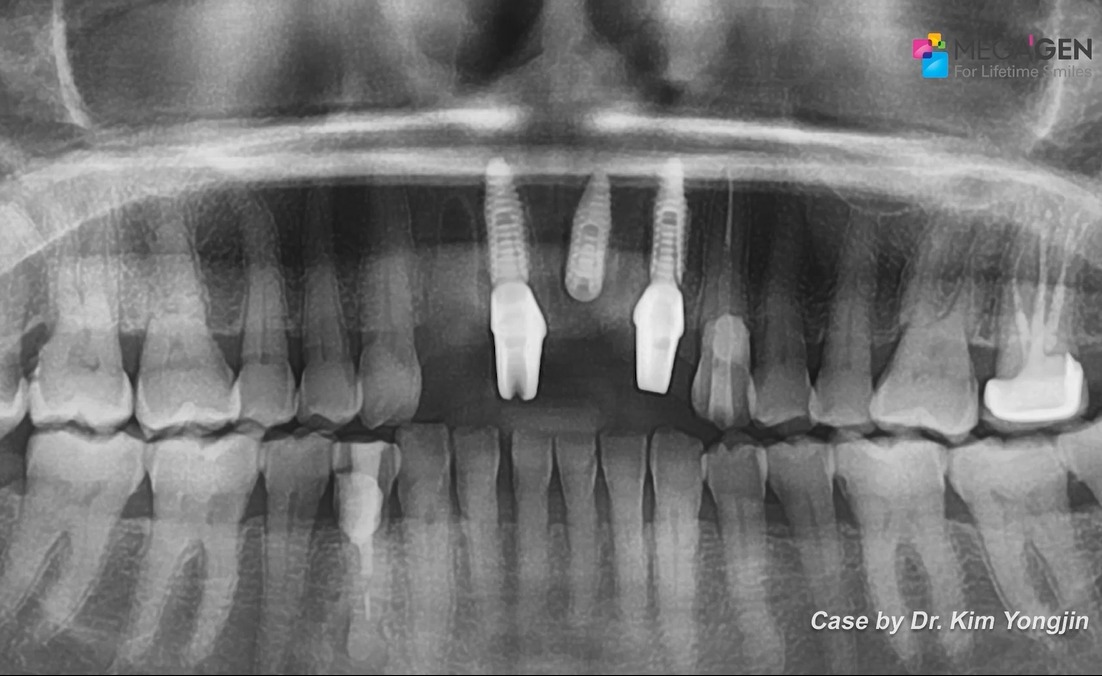

1 2 3 4 8